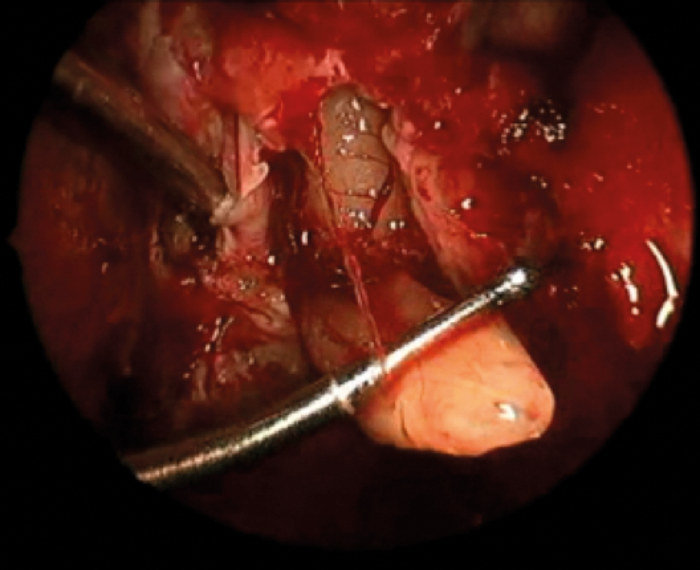

Figure 3. Intraoperative endoscopic view of delivery of the olfactory bulb prior to resection during removal of an olfactory neuroblastoma. The inferior surface of the frontal lobe can be visualised superiorly.

While the nose has long been used for access to pituitary lesions, the excellent visualisation provided by endoscopic techniques combined with the ability to close skull base defects with high success rates, led to the concepts of transnasal approaches to the anterior, middle and posterior fossas (Figure 3). The desirability of avoiding brain retraction and the reduced morbidity associated with transnasal approaches has now led to the widespread adoption of transnasal intracranial access and the variety of lesions accessed through these approaches continues to grow.